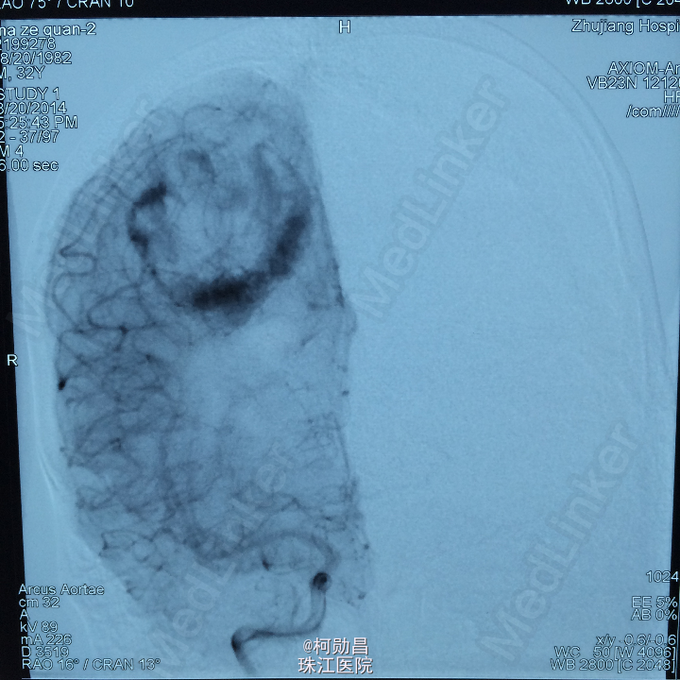

主诉:头痛伴右上肢麻木无力两个月,加重七天 病史:两个月前出现头痛,走路不稳,右上肢无力,不能持物,过去两个月曾有两次癫痫全面发作,发作时意识丧失,但无尿失禁及舌头咬伤。查头MRI示右侧顶叶占位,考虑脑膜瘤。

查体:巴氏征阳性,左侧肢体感觉减退,肌力正常,余无特殊阳性。 辅助检查:查头MRI示右侧顶叶占位,考虑脑膜瘤。

诊断:左侧顶叶占位 处理:行DSA检查,提示肿瘤染色,予PVA颗粒行血管内栓塞治疗。

术后再予开颅手术治疗,书中见供血动脉闭塞,出血量少。